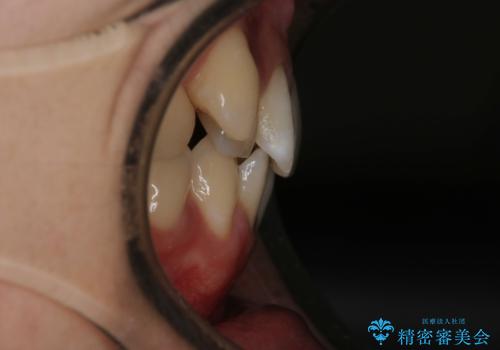

- 上の八重歯と下の歯のがたつきを主訴に来院されました。

矯正検査の結果、抜歯はせずに

臼歯を遠心移動させ、歯列をワイヤーで整えることでスペースを確保し、IPR(歯と歯の間を削る処置)を加えて歯並びを綺麗にする治療計画を立てました。